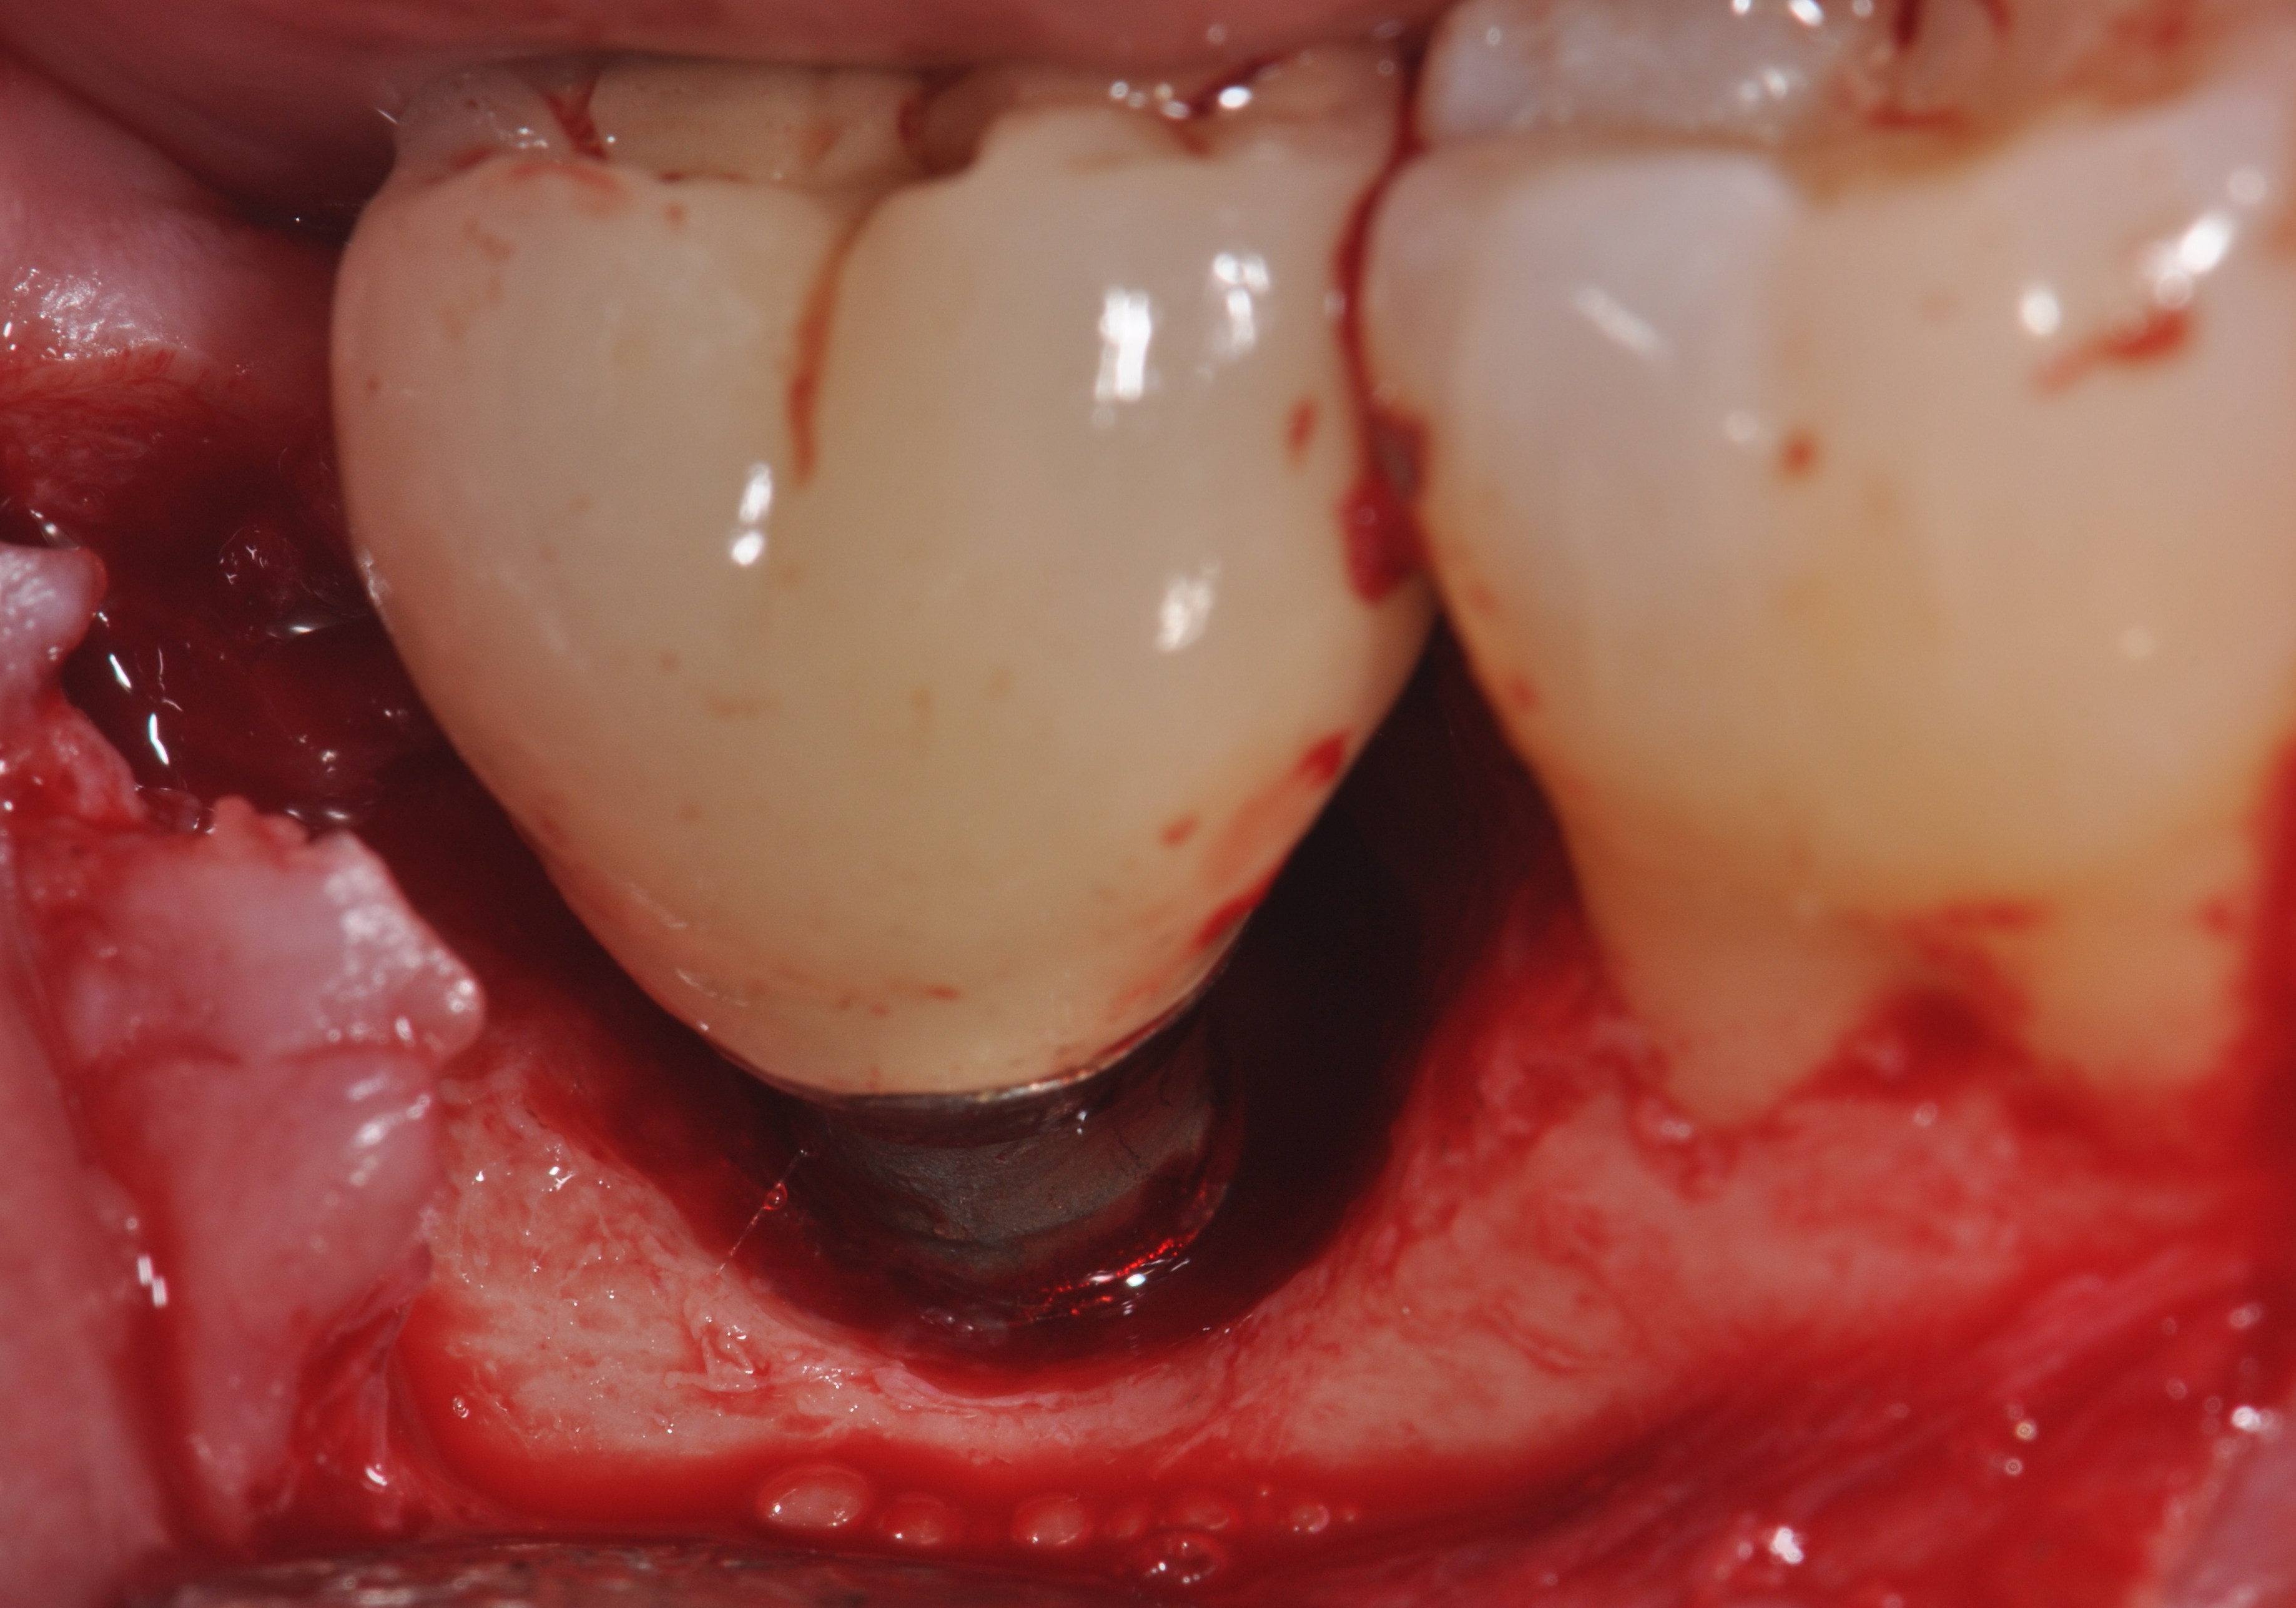

Fig 9. Clinical view of this lesion shows the circumferential pattern to the bone loss.

Figure 9